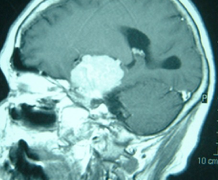

エピソード 朝起こる頭痛、吐き気、高血圧?これは危ない! ここで”朝起こる頭痛”となると、我々脳外科の世界では、その症状の組み合わせでもっとも危険な疾患は「脳腫瘍」です。このブログは、"高血圧”に特化しているサイトですが、高血圧以外の他の疾患のこともきちんと、お話ししておく必要があると思います。高... 2015.11.23 エピソード症状